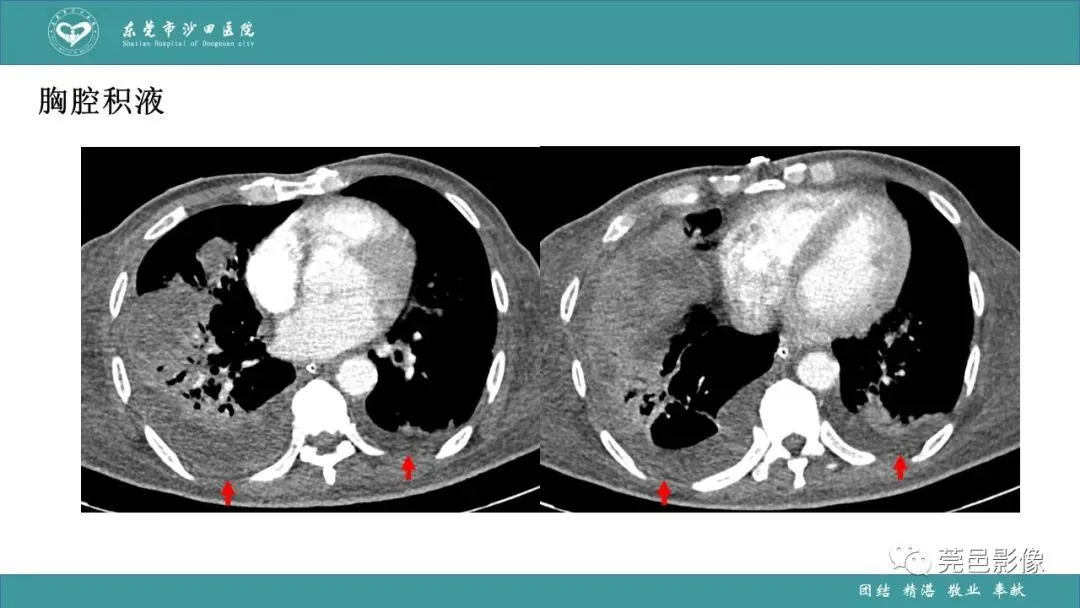

>课件 | 肺炎克雷伯杆菌肺炎影像学诊断与鉴别诊断

课件 | 肺炎克雷伯杆菌肺炎影像学诊断与鉴别诊断